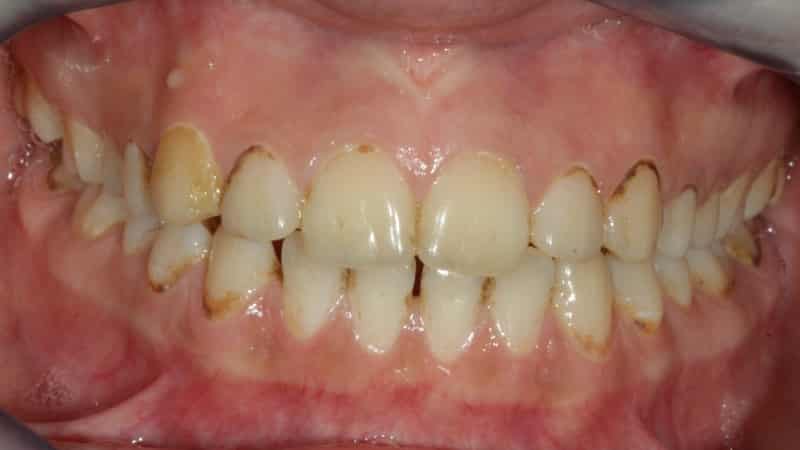

Из всех видов кариеса прикорневой считается наиболее опасным, так как он разрушает зубы, их корни и каналы. Это явление особенно часто наблюдается у пожилых пациентов и может привести к потере зубов. У таких больных часто возникают вопросы о том, что такое пришеечный кариес, как его лечить, какие причины его возникновения и как он выглядит на фотографиях. Давайте рассмотрим эти аспекты более подробно.

Данное заболевание проходит через несколько стадий, каждая из которых имеет свои признаки и методы лечения. Стадии развития кариеса могут быть следующими:

- Вторая стадия — на этом этапе развивается поверхностный кариес, который приводит к разрушению эмали. Появляется темное пятно, а также боль при употреблении сладкого, горячего, кислого, соленого и холодного. Лечение включает в себя препарирование и пломбировку пораженной области.

- Средний кариес — характеризуется размягчением дентина, прогрессированием кариеса и усилением болевых ощущений при приеме пищи и напитков с различной температурой и вкусом. Стоматолог удаляет часть нависающей эмали и размягченного дентина, после чего проводит пломбирование.